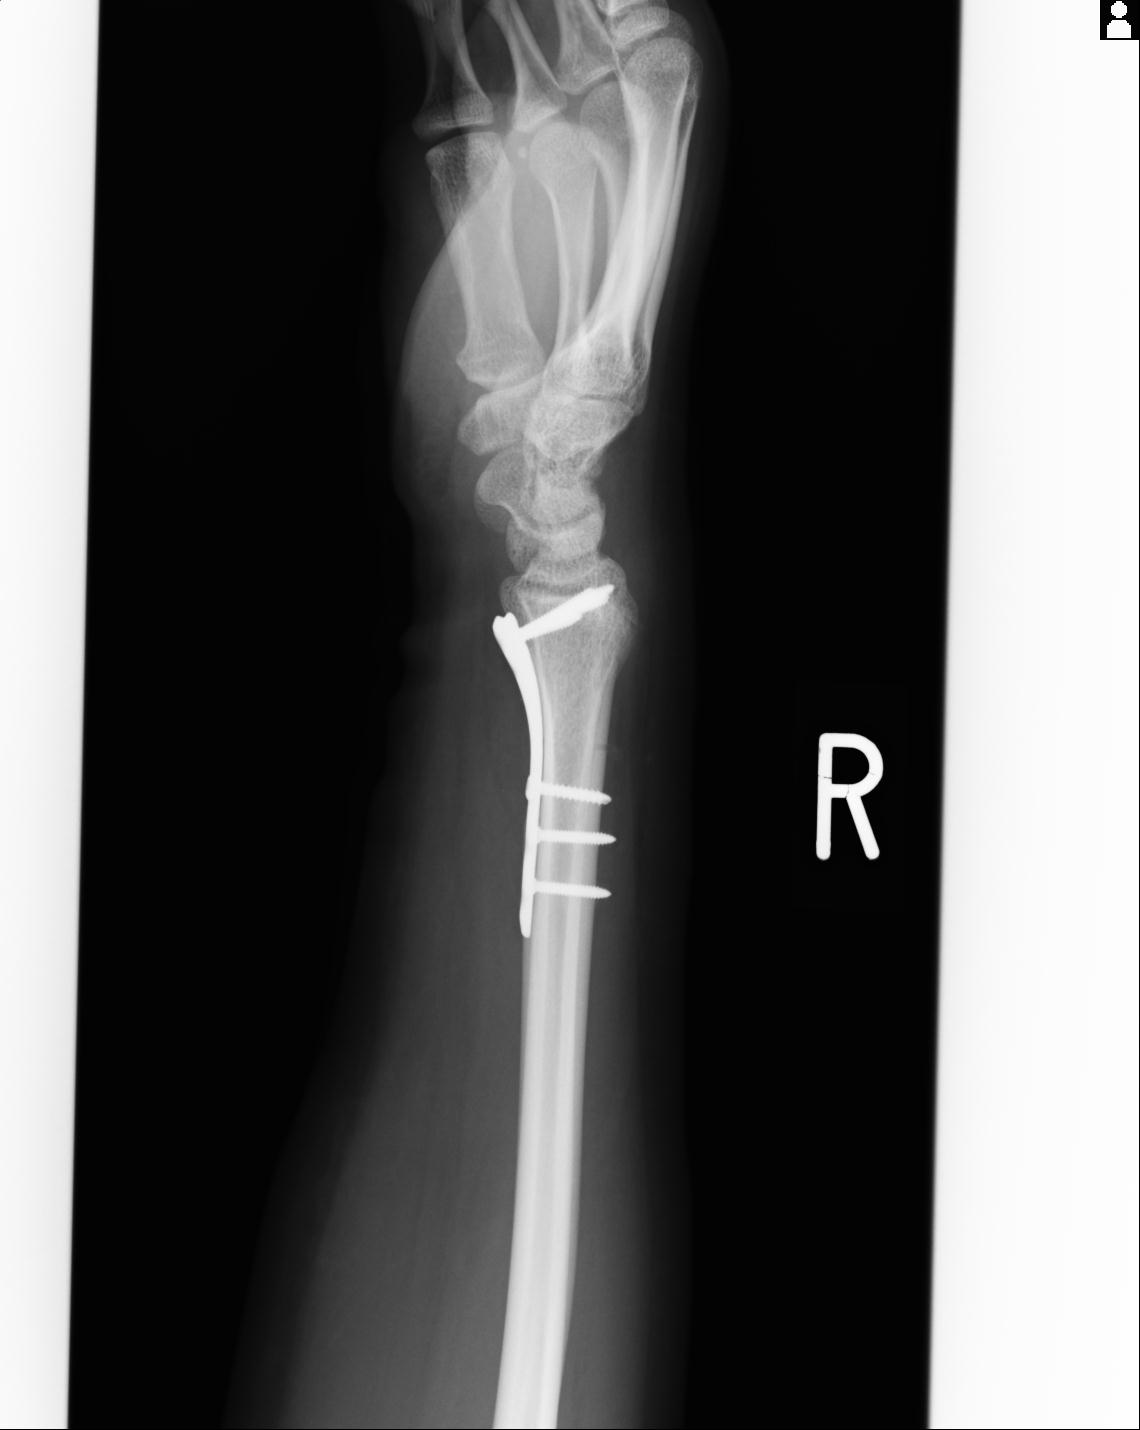

102803 1/12(キウスなし) 1/27 左下腿 4R 30歳女性 左脛骨軸内釘